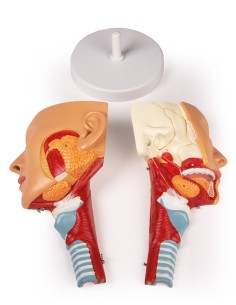

3B Scientific, modello anatomico funzionale di laringe: W42503

Dal cranio in 22 parti con incastri magnetici ai modelli di colonna vertebrale, da quelli di articolazioni a quelli di cuore, ogni pezzo della nostra collezione è progettato per un’immersione totale nello studio dell’anatomia umana. I nostri modelli, realizzati tramite scansioni di ossa vere, garantiscono un’esperienza tattile autentica e una fedeltà di peso quasi identica agli originali.

Essenziali per studenti e professionisti, i nostri modelli anatomici sono strumenti didattici che permettono di osservare le strutture anatomiche con precisione, eliminando la necessità di dissezioni o studi invasivi. Sono inoltre utili per spiegare ai pazienti le patologie, rendendo la comunicazione più efficace e risparmiando tempo prezioso.